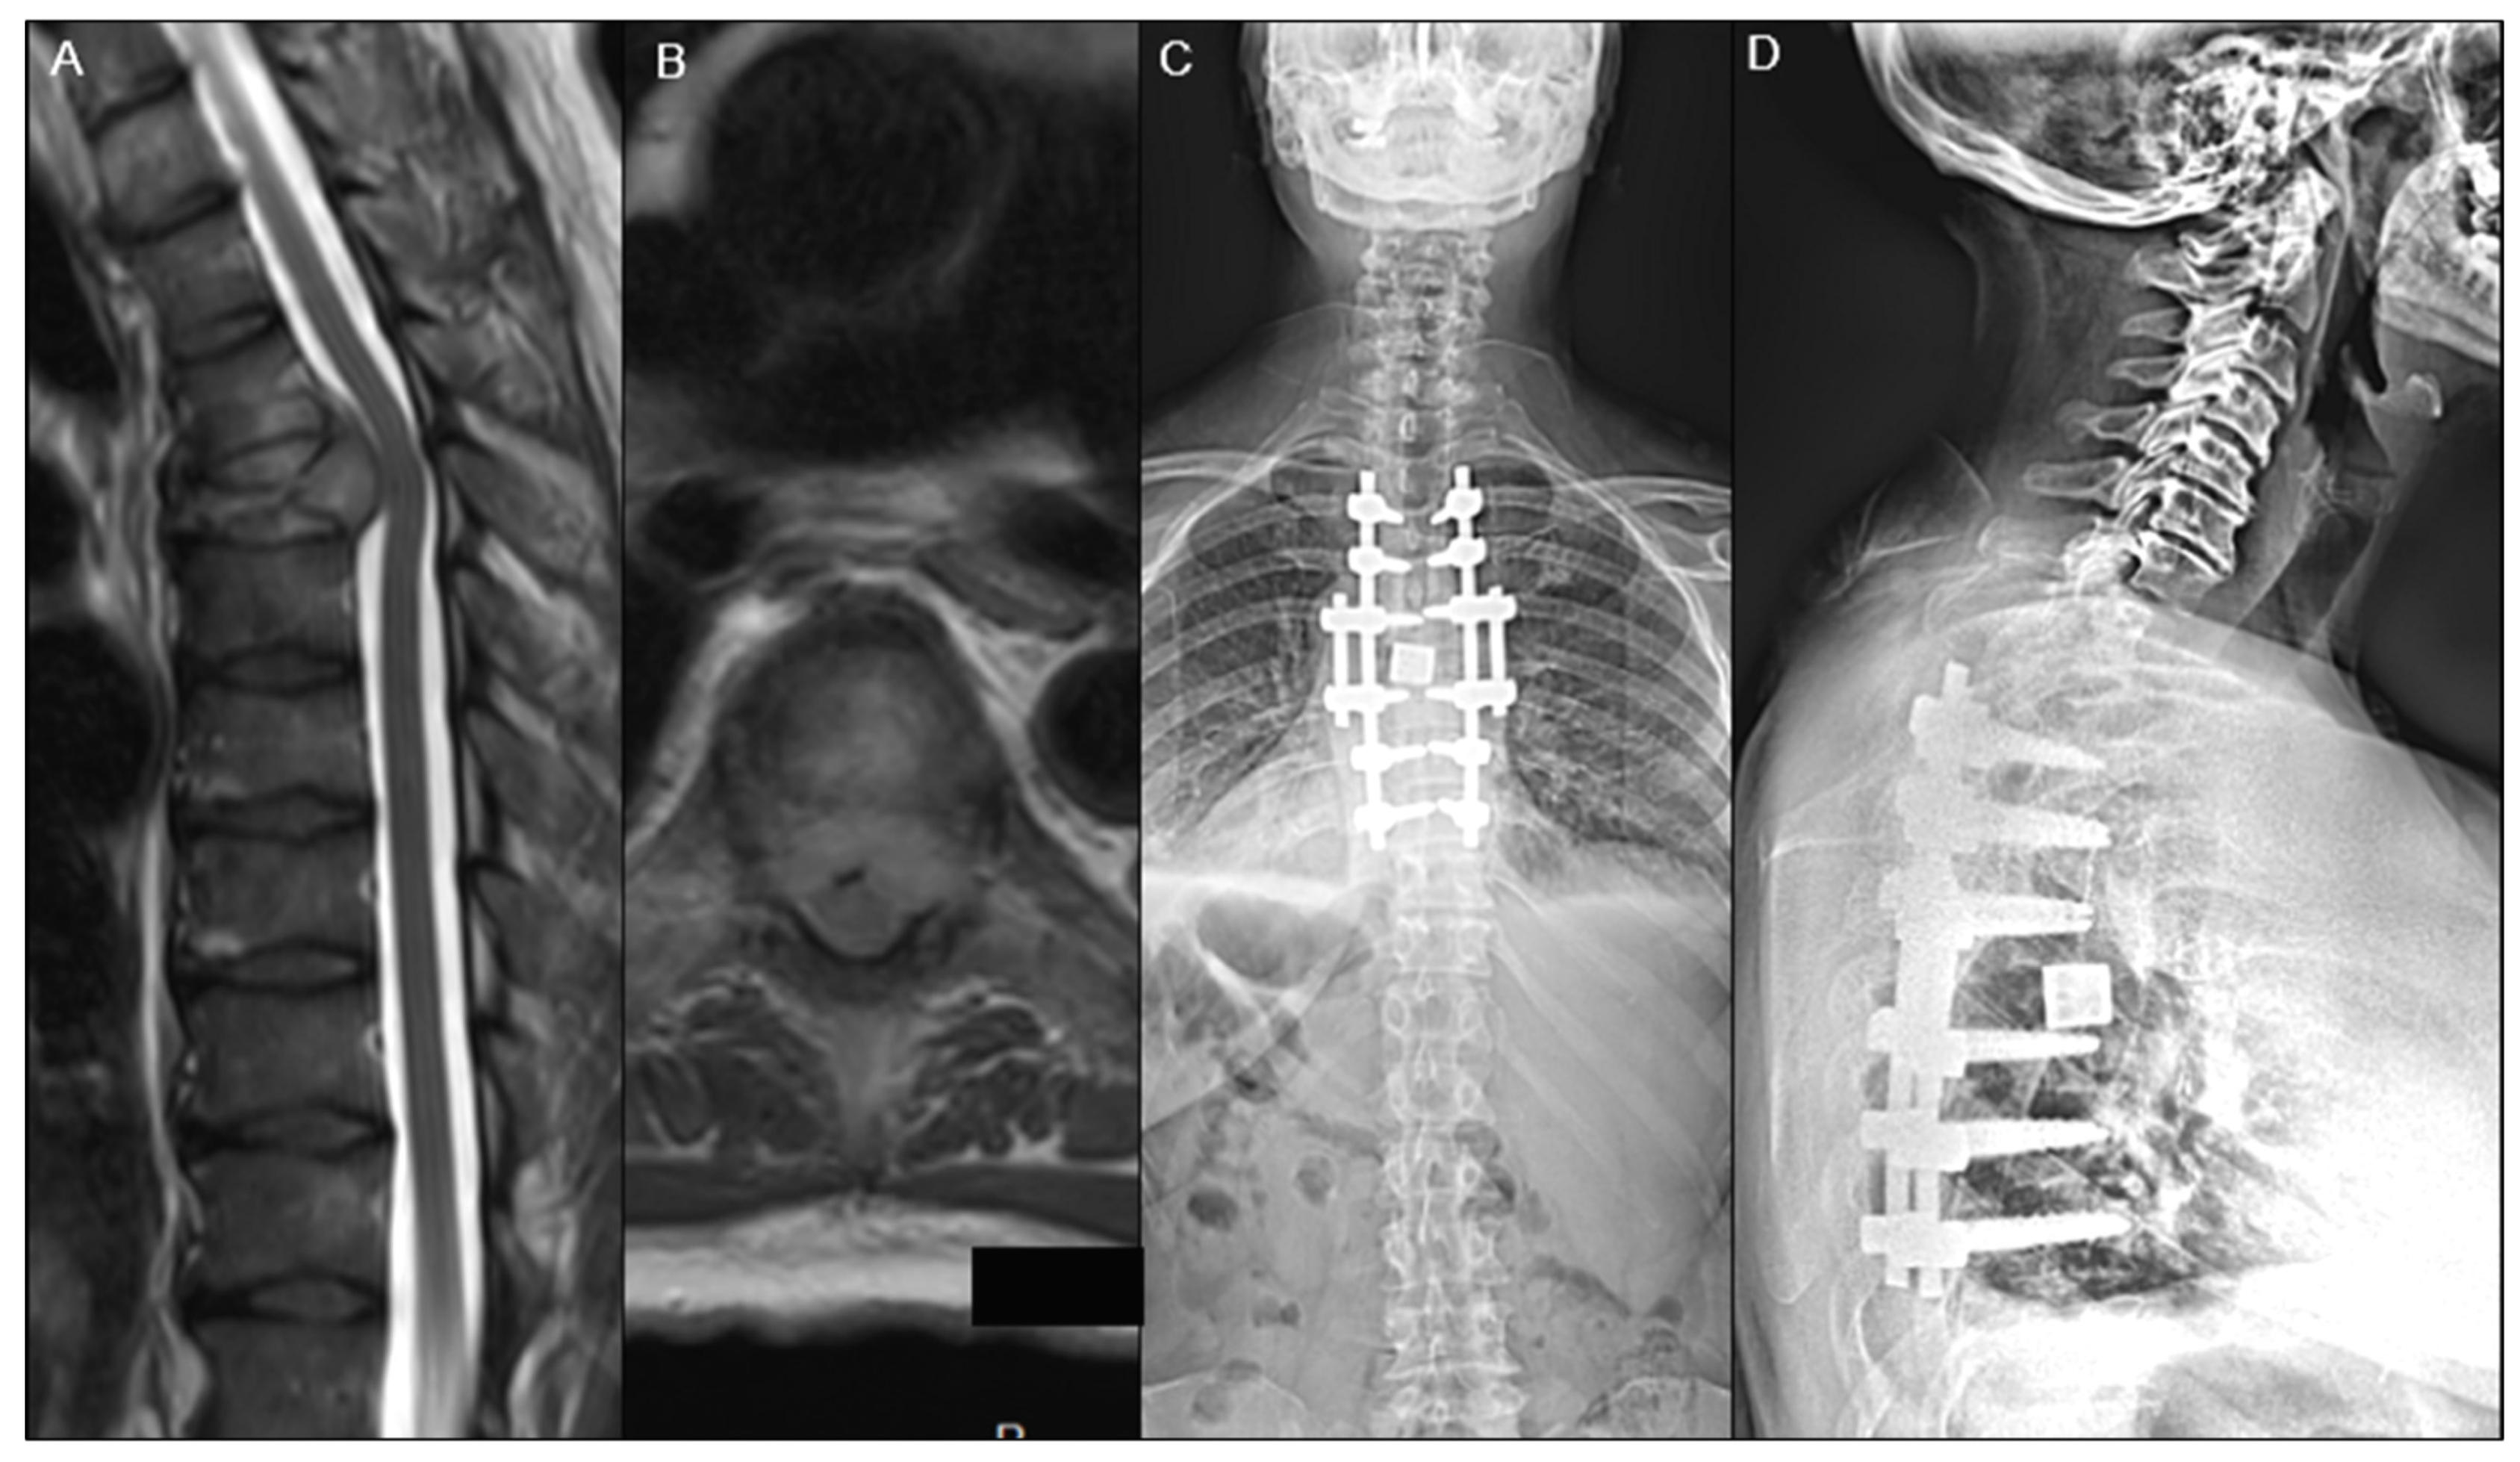

| Tumor Locations, n (%) | 0.351 | |||

| Cervical | 40 (12.9%) | 19 (11.8%) | 21 (14.0%) | |

| Cervico-Thoracic | 11 (3.5%) | 5 (3.1%) | 6 (4.0%) | |

| Thoraco-lumbar | 184 (59.2%) | 103 (64.0%) | 81 (54.0%) | |

| Lumbar | 76 (24.4%) | 34 (21.1%) | 42 (28.0%) | |